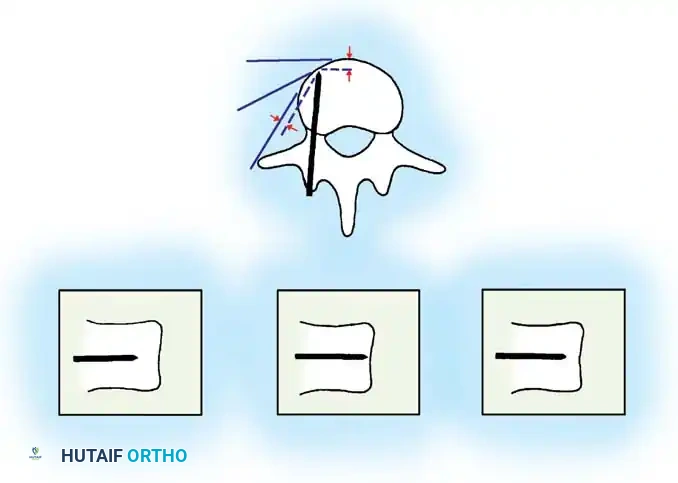

The Moe Technique (Lumbar Spine)

In the lumbar spine, the facet joints are oriented in a more sagittal plane, necessitating a modified approach.

Fig. 38-27: The Moe technique adapted for lumbar facet fusion, addressing the sagittal orientation of the joints.

- Utilize a small osteotome or a needle-nose rongeur to resect the adjoining joint surfaces.

- This creates a distinct rectangular defect within the sagittally oriented joint space.

- Pack this defect forcefully with cancellous bone graft.

- Proceed to decorticate the entire exposed posterior elements (laminae and transverse processes) using Cobb gouges, always directing force away from the spinal canal.